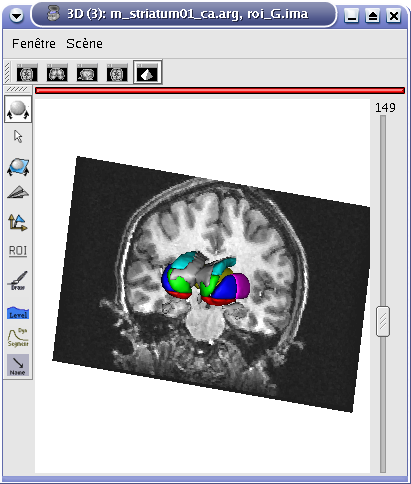

Objects fusion enables to create a new object from 2 or more other objects. Indeed, if you only put two volumes in the same window, you will see only one. To see the two volumes, you need to mix voxels from the two volumes in order to obtain a new volume. Note that fusionning more than 2 objects is only possible since 1.30 version. Besides, several new features have been added for fusion management. Several fusion combinations between objects are available,but for the moment, let’s see a fusion between two 3D volumes for example:

STEP 1: Load the images to merge. Here, we will fusion an anatomy and the brain mask obtained from BrainVISA anatomical pipeline.

Example of a linear fusion between two 3D volumes¶